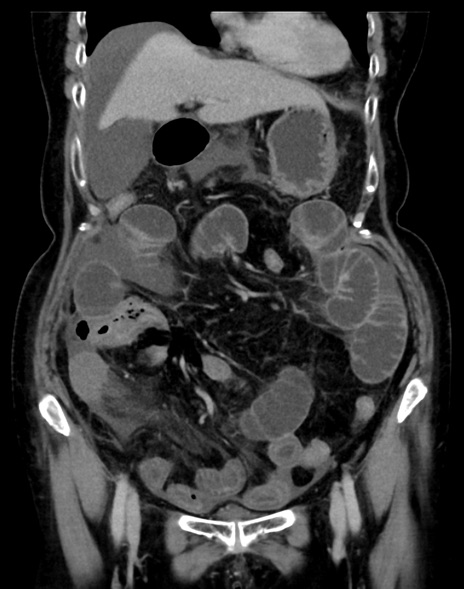

(横断像)1日半後